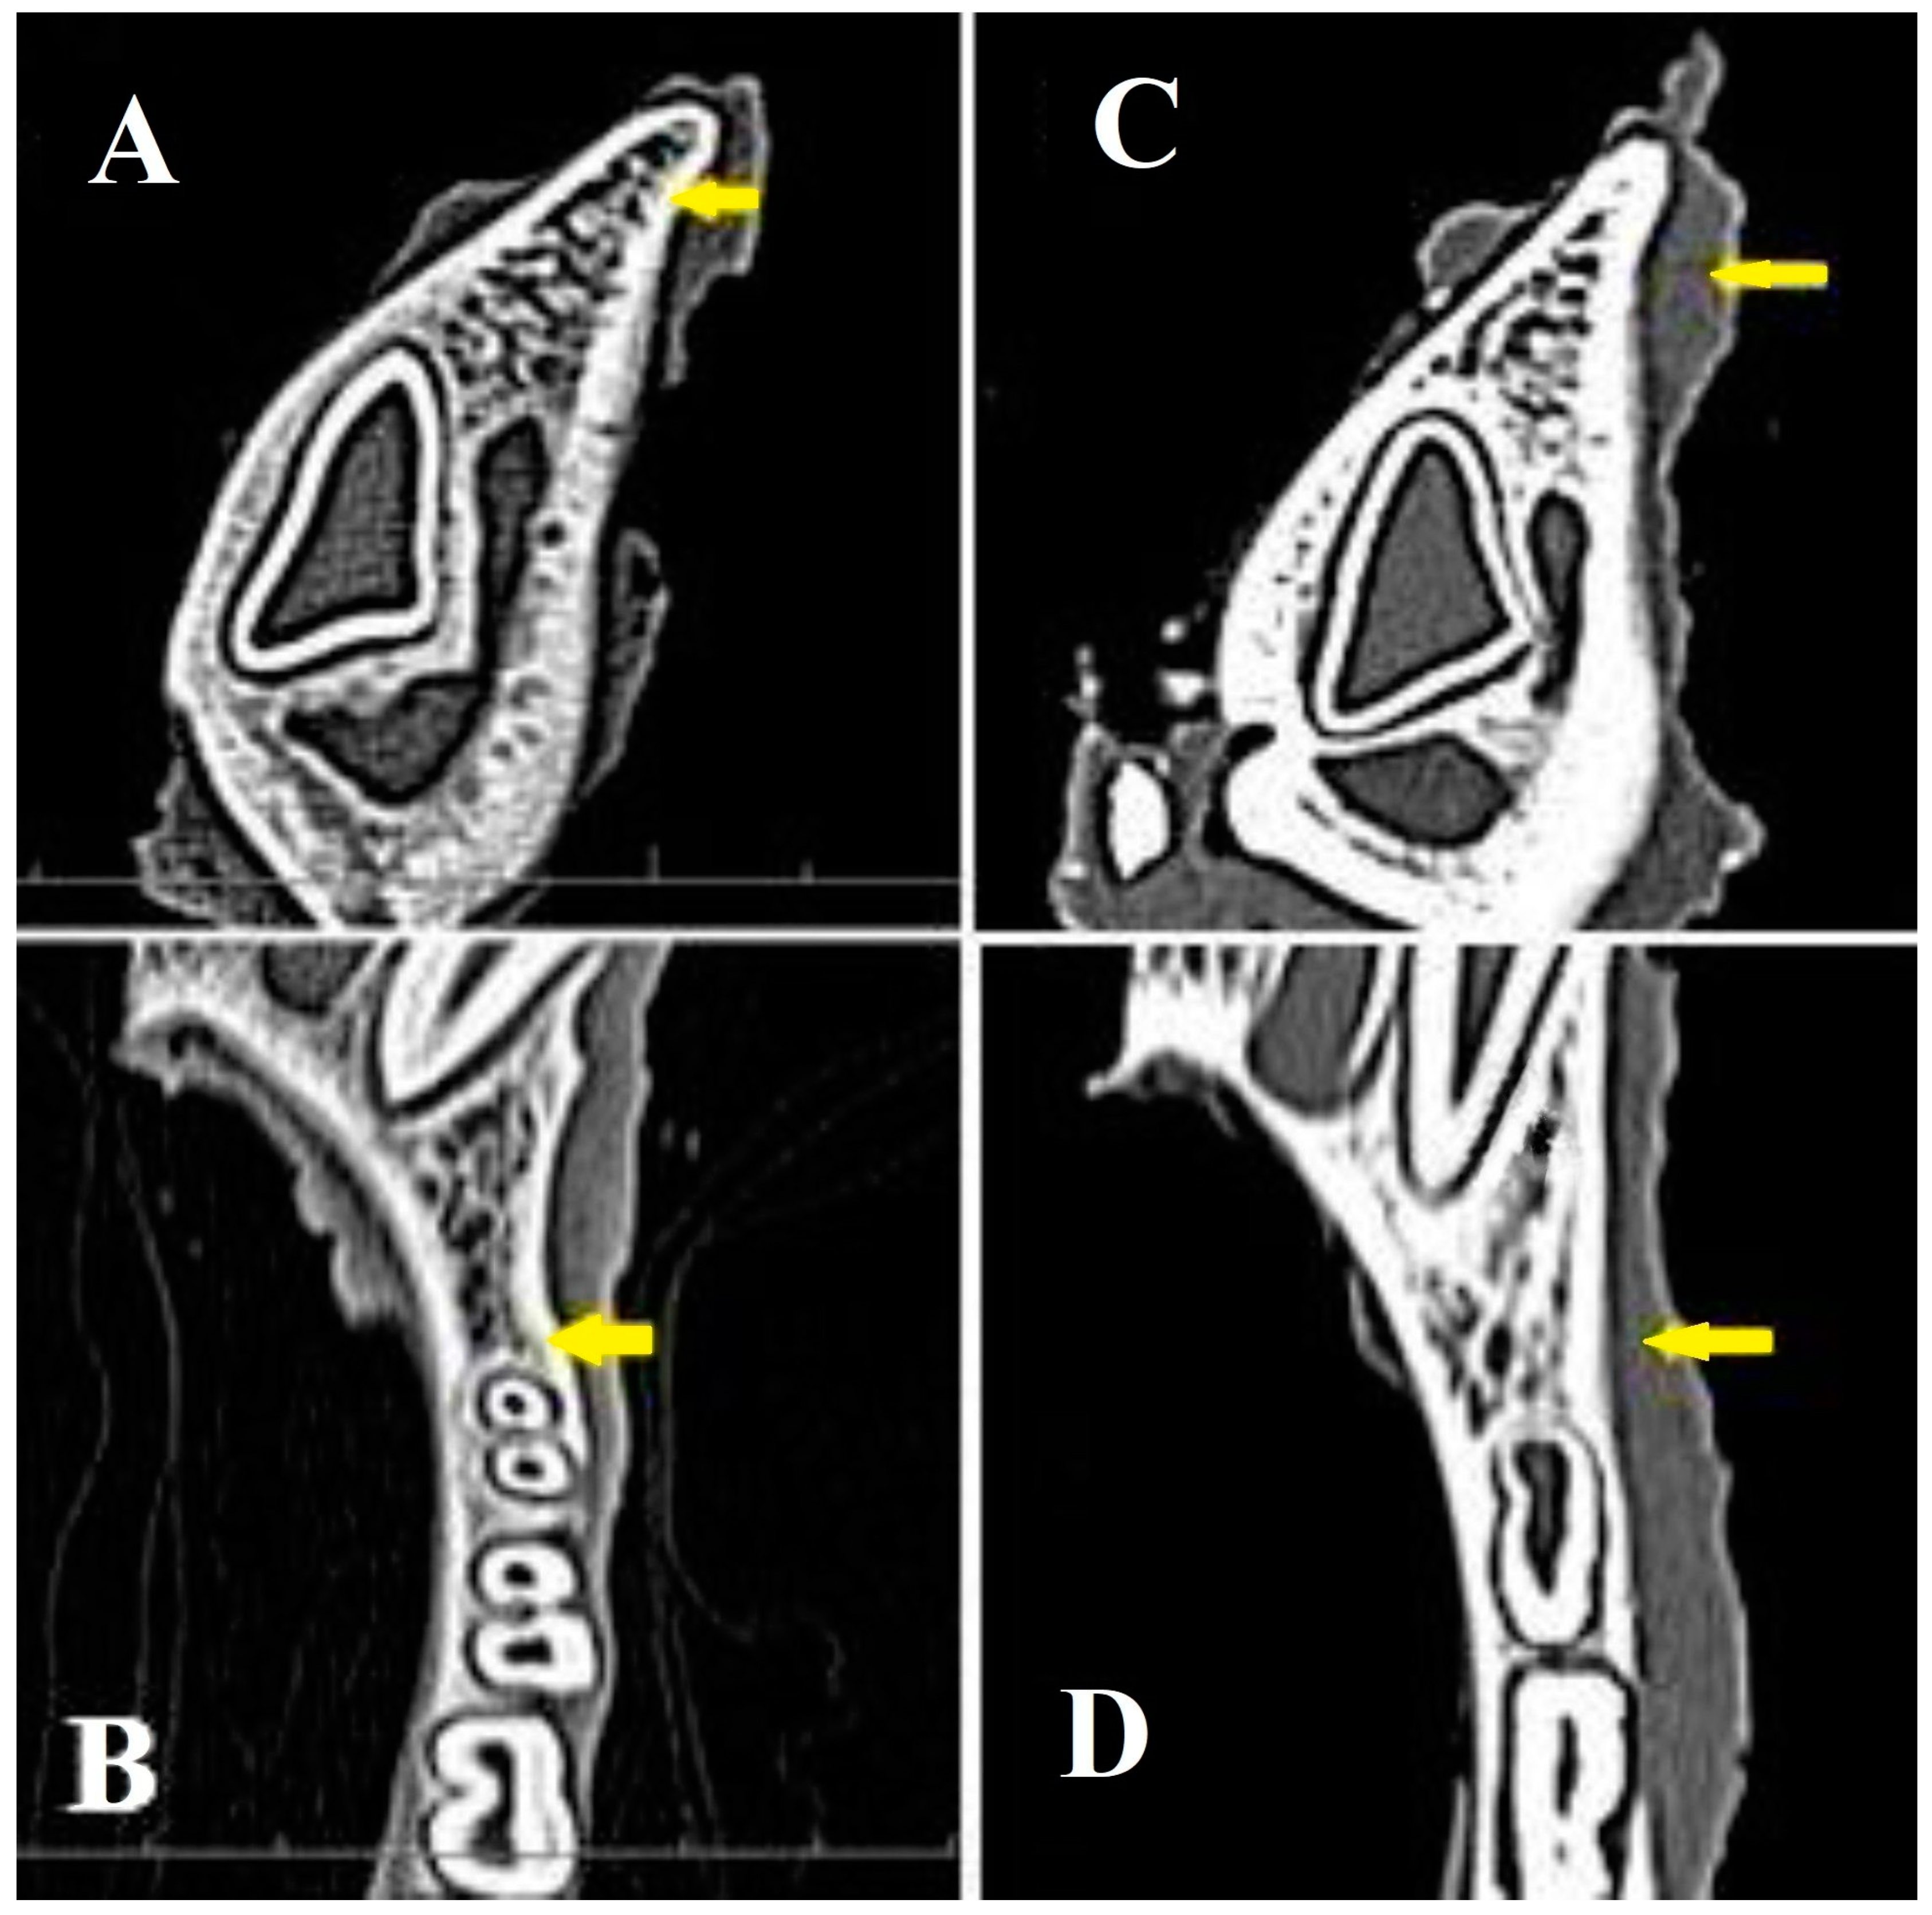

3.5. Radiological Evaluation